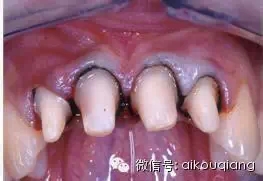

四、正確的排齦方法

1.干燥、隔濕基牙。

2.選用與齦溝寬度一致的排齦線,將排齦線起始斷放置于預(yù)備基牙的近中或遠中鄰面,圍繞預(yù)備的基牙纏繞一周,即360度(一般鄰面齦溝較深,從這里起始,可以為以后補償做好準(zhǔn)備)。

3.用牙周探針或?qū)S门琵l器等排齦工具,使排齦工具與水平方向約呈45度, 排齦工具尖端壓緊排齦線沿牙齒壁慢慢下滑,推牙齦向側(cè)方及根尖向移動。避免損傷上皮組織附著齦、結(jié)合組織附著齦。

4.如齦溝較深, 將到達鄰面的排齦線繼續(xù)纏繞預(yù)備的基牙,繼續(xù)排齦。

5.排齦后,應(yīng)使排齦線與游離齦緣上端平齊、連續(xù)、兩者清晰可見。